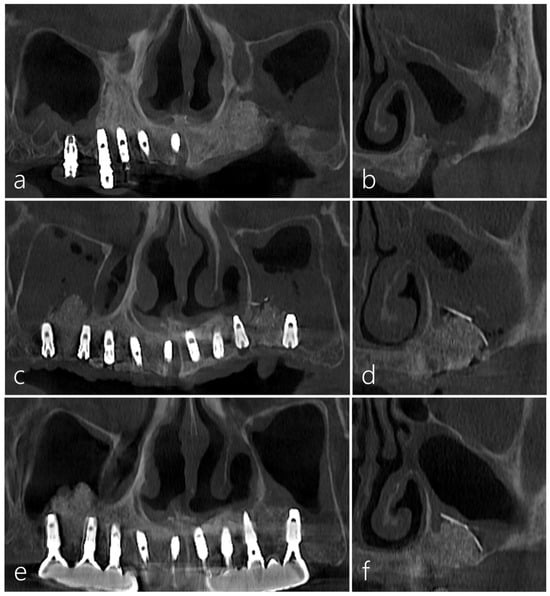

2.1. Case 1